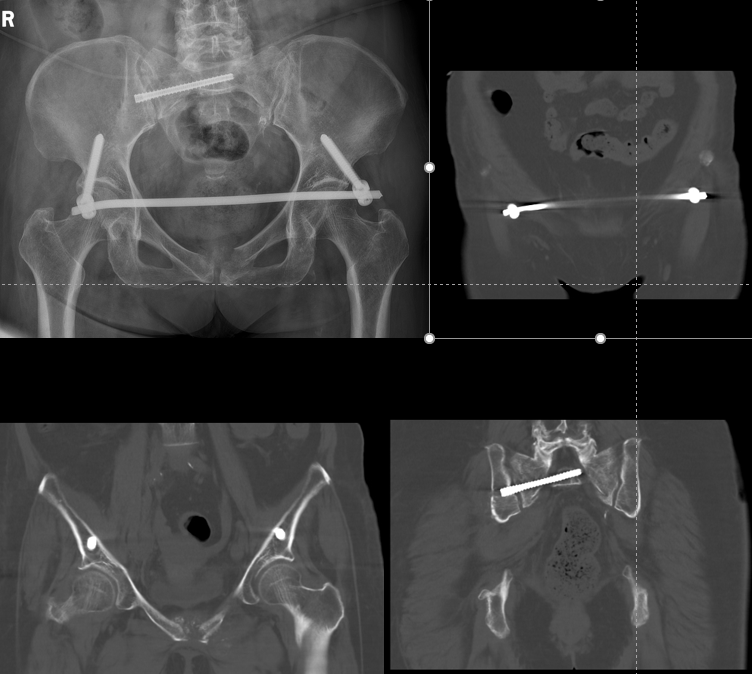

王某某,女 性,61岁,因“腰部及双下肢疼痛2个月”入院,患者2个月前在家中不慎摔倒,臀部着地,逐渐出现腰部及双下肢的疼痛感,行走困难,患者拄着双拐来我院就诊,经过查体检查后,排除腰椎病变,诊断为骨盆骨折(Tile B3型,骨盆后环骨折伴骨盆不稳)。

在上级专家指导下,科室团队确定了现行给予骨盆内置外架恢复骨盆稳定,再给予经皮骶髂螺钉植入固定后环的手术方案。

◆术后复查影像